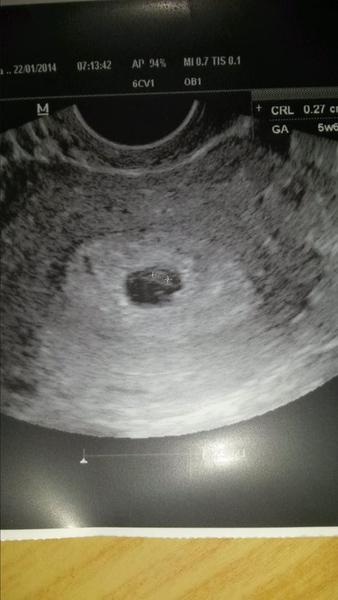

@ajkalak ahojte kočky moje.tam dnes sme mali sono dr povedala ze dobre.len som troska laknuta lebo podla MS som 7+2 a ona mi povedala ze zodpovedam 5+6 tt.babatko ma 2,7 mm a dalsia kontrola o tyzden. Srdiecko este nevidela i ked povedala ze nieco sa jej mari ze blika ale nechce to na 100% povedat ze je to tak. Hm tak uvidim aj som kludna ze plodik bol ale aj troska taka znepokojena tou velkostou 😒 dam vam aj fotecku len nie som na pocitaci tak hned ako sa dostanem dam 😉

@afrika ahaaaa tak supeeer mojaaaa joj ani si nevies predstavit ako si ma potesila. lebo mne to vychadza podla mrchy 7+2 a podla sona 5+6 tak som sa lakla ale tak to je mozno tyzden rozdiel ani nie dva vsak? joj ani nevies ako si ma ukludnila 🙂 dakujeeeem. no ona naznak videla vravi ze nieco tam blika ale nevidela dobre tak si nebola sto percent ista 🙂 🙂 pridavam fotecku 🙂